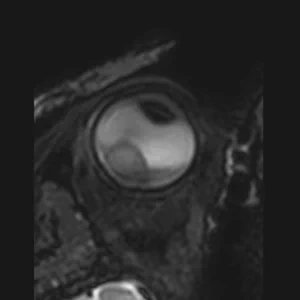

• T1 & T1Gd

T1 & T1Gd

Contrast enhanced scans to differentiate the lesion and retinal detachment.